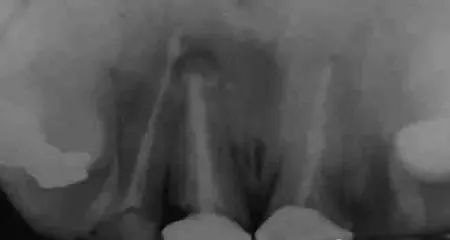

图1 X线显示上11根尖息肉阴影